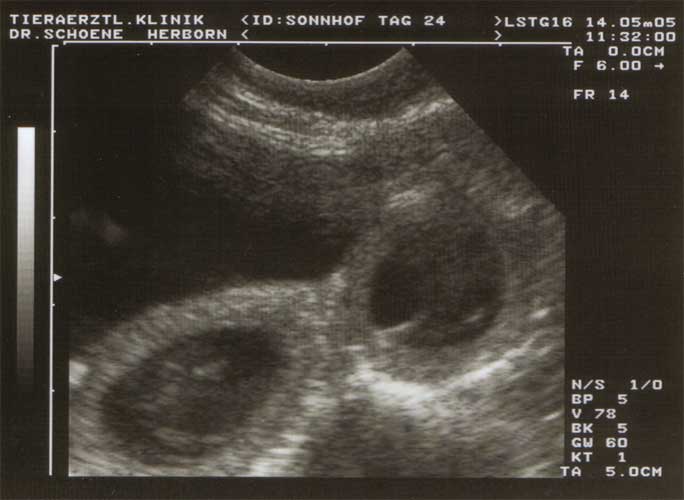

20./21.04.05: Janni wurde von Quills Black Peter Pike "Pikey" gedeckt! Wir erwarten unseren C-Wurf somit um den 22. Juni 2005. Janni kurz vor der erwarteten Geburt am Tag 60 nach Deckung:

Janni während ihrer Trächtigkeit am 13.06.05, 9 Tage vor errechnetem Geburtstermin:

Oben erkennt man deutlich zwei Früchte;

auf dem unteren Foto sieht man in zwei unterschiedlichen Ebenen jeweils zwei Früchte: